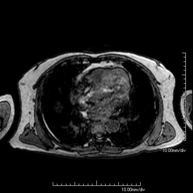

- Chest MRI

This non-invasive diagnostic procedure uses an electromagnetic field and radio waves (from a transmitter and receiver) to acquire high-definition anatomical images of the chest. It is a radiation-free procedure. It is indicated for lung lesions in which infiltration of the mediastinum or thoracic wall must be ruled out, to differentiate between solid and cystic chest lesions, etc. Sometimes paramagnetic contrast (gadolinium) must be used to complete the study.